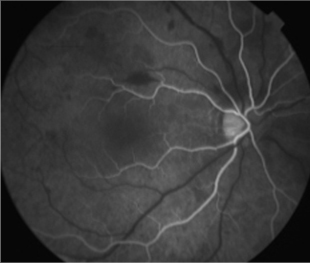

2 meses: disminución de manchas algodonosas y hemorragias con mejoría de circulación

OD - 0,50 esf 0,9 +2

OI -0,25 esf 1,00